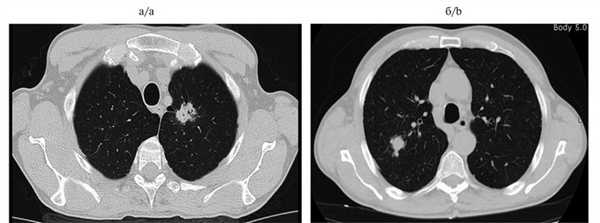

Анамнез заболевания: на фоне 40-летнего стажа курения (по 1 пачке в день) и хронической обструктивной болезни легких (ХОБЛ) в ноябре 2007 г. у больного появилась боль в грудной клетке справа. При обследовании в поликлинике по месту жительства по данным рентгенографии и КТ органов грудной клетки выявлено узловое образование в верхней доле левого легкого. Обследован в ЦНИИ туберкулеза РАМН. После 2-месячного противотуберкулезного лечения рентгенологической динамики не отмечено. Заподозрен рак легкого. Направлен к онкологу. Обратился в МНИОИ им. П.А. Герцена. При обследовании в институте по данным КТ органов грудной клетки в апреле 2008 г. выявлено опухолевое образование в верхней доле левого легкого, а также в верхней доле правого легкого, трактуемое как первично-множественный синхронный рак легких (рис. 1). Рис. 1. Компьютерные томограммы органов грудной клетки. а, б — объяснение в тексте. Диагноз верифицирован морфологически посредством последовательных трансторакальных пункций образований под контролем КТ и УЗИ. Цитологическое исследование: плоскоклеточный ороговевающий рак (слева); низкодифференцированный плоскоклеточный рак (справа).

При КТ органов грудной клетки (26.02.08) обнаружены периферическое солидное узловое образование верхней доли левого легкого с неровными бугристыми контурами размером 1,5×1,7 см (рис. 1, а) и частично солидное периферическое узловое образование в верхушечном сегменте правого легкого со спикулообразными контурами размером 1,2×1,0 см (см. рис. 1, б). Трахея и бронхи (1—3-го порядка) проходимы, не деформированы. Жидкости в плевральных полостях не выявлено. Средостение структурное. Внутригрудные лимфатические узлы не изменены. Мягкие ткани и костные структуры грудной клетки без изменений.